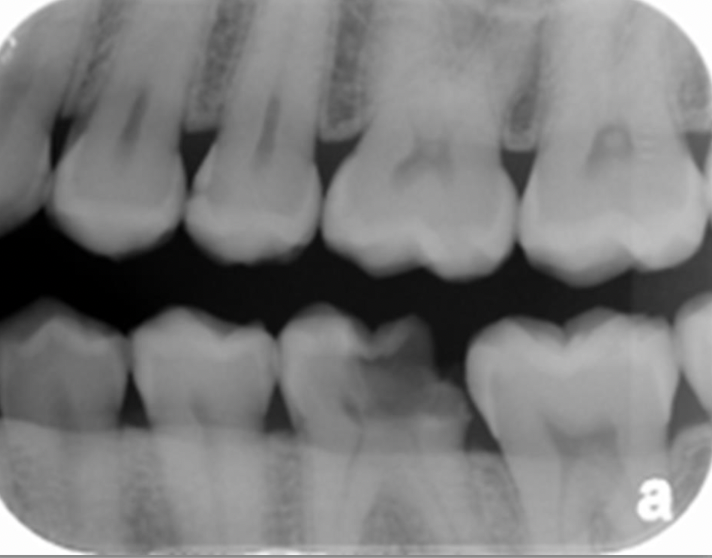

What type of radiographs are seen in the following images?

periapical radiographs

31

Detect the caries in the following images: